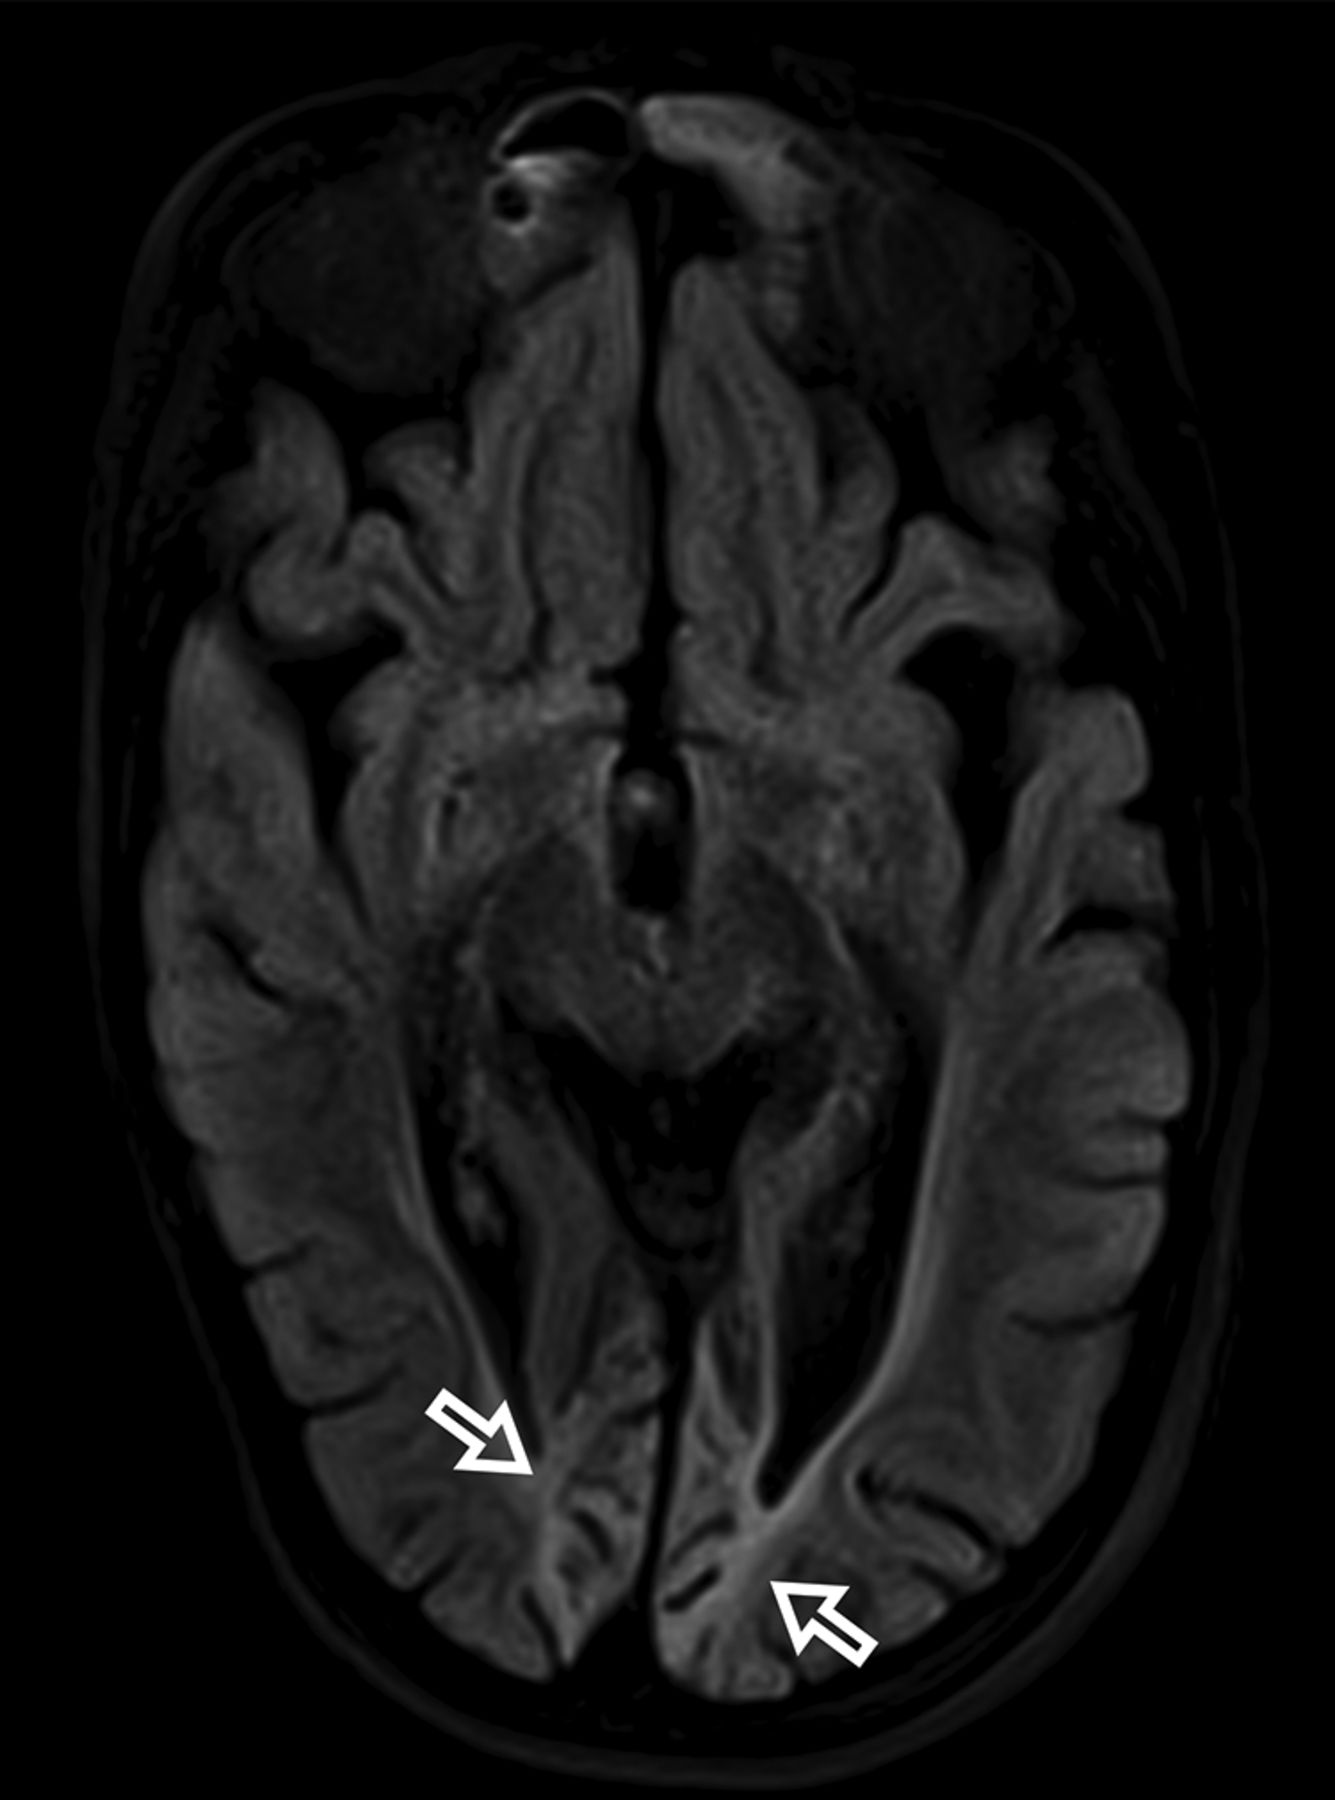

At diagnosis, brain MR imaging findings were abnormal in most patients (n = 12, 92%). The most common brain MR imaging findings were unilateral or bilateral perirolandic signal changes (n = 7, 54%) (Fig 1) and unilateral or bilateral thalamic signal changes (n = 10, 77%) (Fig 2). Perirolandic signal abnormalities were unilateral in most cases (n = 5, 71%) and were more frequently seen only affecting the precentral or both the pre- and postcentral gyri. Half of the thalamic changes were unilateral (n = 5, 50%). Simultaneous perirolandic and thalamic signal changes occurred in 6 patients (n = 6, 46%). An association of EPC (clinically/EEG) and perirolandic signal changes was present in 6 patients (n = 6, 75%), and an association of EPC (clinically/EEG) and thalamic signal changes, in 7 patients (n = 7, 87.5%). Two patients with EPC (clinically/EEG) did not present with perirolandic signal abnormalities. The findings positive for lesions overall were on the DWI of 10 patients (n = 10, 83%), on the T2WI of 9 patients (n = 9, 75%), and on FLAIR of 7 patients (n = 7, 58%). In 4 patients, DWI was the only sequence with abnormal findings. The occipital lobe was affected in the early brain MR imaging in 2 patients (n = 2, 15%). Signal changes in other brain regions were found in 5 patients (n = 5, 42%), involving multiple regions, namely the cerebral white matter, insula, putamen, caudate nucleus, fornix, cerebellar vermis, and also the frontal and occipital lobes. One patient did not present with either perirolandic or thalamic changes but instead presented with a diffuse pattern similar to that of leukoencephalopathy, with restricted diffusion in the white matter and white matter tracts (Fig 3). Three patients had an abnormally high lactate peak on MR spectroscopy. None of our patients had ASL or other perfusion-weighted imaging at the time of diagnosis. T1 and T2* imaging and SWI had negative findings at the time of diagnosis.

MR imaging thalamic signal changes in 3 different patients with POLG-related disorders (A, A 9-month-old female), (B, A 3-year-old female), and (C, A 3-year-old male). Thalamic signal changes were also variable with varying degrees of conspicuity. A, DWI. Signal changes were subtle and focal with restricted diffusion in the right thalamus (open arrow). B, FLAIR. Signal changes involved both thalami, more conspicuous on the left side (open arrows). C, T2WI. Signal changes were bilateral and symmetric involving both thalami (open arrows).

Thalamic signal changes were also frequent at the time of diagnosis and on follow-up imaging. Unilateral or bilateral thalamic involvement was identified in most patients during the onset of their disease. In our cohort, there was no new thalamic involvement at follow-up. On follow-up imaging, thalamic changes had different outcomes: complete resolution, progression from unilateral to bilateral involvement, progression accompanied by volume loss, and fluctuation with periods of an almost-complete resolution and frank progression. Thalamic signal changes were variably detected on DWI, T2WI, FLAIR, or ASL.